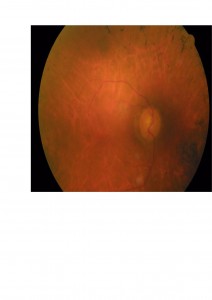

Os presentamos el caso de un paciente atendido en nuestra clínica. Presentaba una aguudeza visual OD 0,3 y OI 0,1 , con cataratas en ambos ojos (mostrada en la foto anterior). En el fondo de ojo presentaba buena coloración de las papilas y en la OCT un edema macular cistoide como os mostramos.